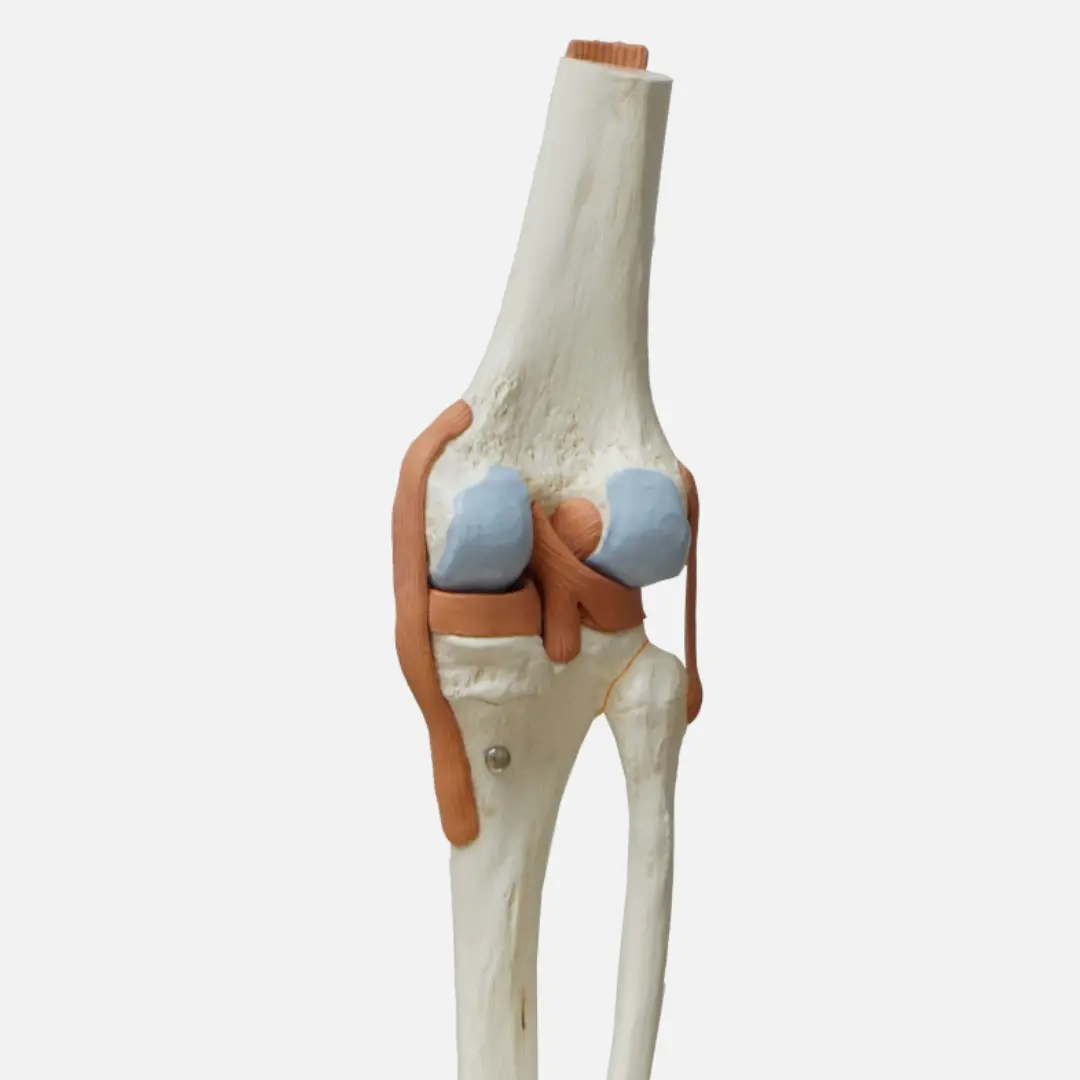

- 관절 연골 및 관절액의 핵심 구성 성분

- 물리적 충격 완화와 연골 손상 회복을 도움

- 관절 연골의 주요 구성 성분

- 연골 재생과 관절 통증 완화에 도움